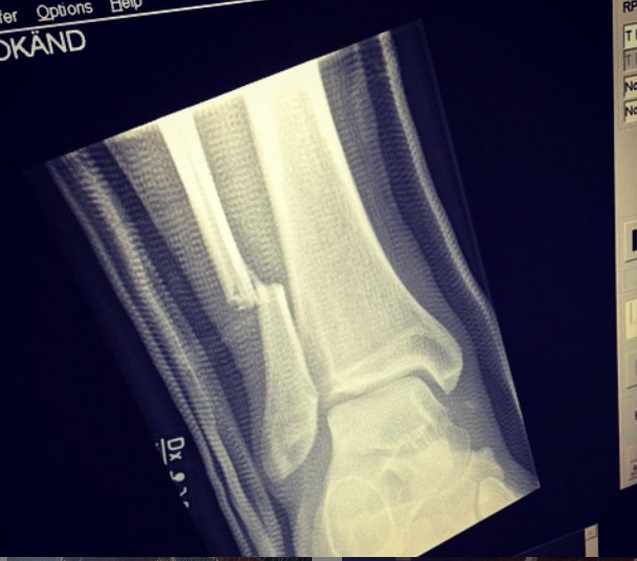

Radiografía muestra la impactante lesión que sufrió líder de Foo Fighters

Tras el recital, la banda publicó en Instagram una foto de la radiografía para que sus seguidores vieran la lesión de su vocalista. La imagen acumuló cerca de 65 mil “me gusta” en dos días.